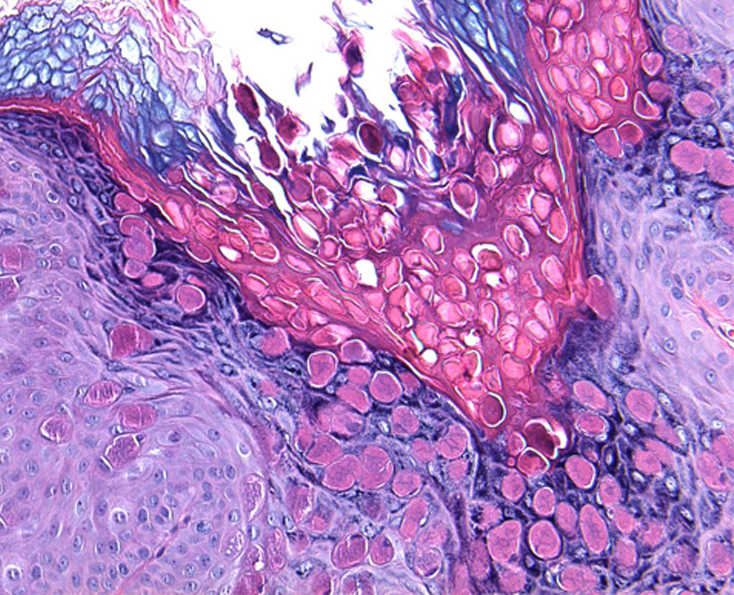

Клинические проявления неинфекционных заболеваний кожи при поражении аногенитальной области в целом не отличаются от таковых другой локализации. Однако целый ряд особенностей пораженной области – разная степень кератинизации эпителия, хорошая васкуляризация, окклюзия и мацерация кожным салом, потом и вагинальным отделяемым, высокий рH кожи (результат расщепления бактериальными уреазами мочевой кислоты с образованием аммиака), трение – нередко приводят к изменениям их клинической картины. Это существенно затрудняет распознавание заболеваний гениталий и перианальной области. Значительное сходство субъективной симптоматики и клинических проявлений дерматозы аногенитальной области имеют с инфекционными, а также предраковыми заболеваниями данной локализации, что нередко является одной из причин поздней диагностики дерматозов и предраков. Ситуация усложняется различием классификаций и терминов, используемых разными клиницистами (акушерами-гинекологами, урологами,

дерматологами) и морфологами, что приводит к непониманию и затрудняет преемственность (комплексный подход) в ведении этих пациентов.

Лечение дерматозов аногенитальной локализации нередко представляет сложную задачу и требует междисциплинарного подхода. Основные подходы к лечению дерматозов данной локализации включают восстановление кожного барьера, назначение противовоспалительных препаратов, в частности топических глюкокортикостероидов и/или топических ингибиторов кальциневрина, реже – системных глюкокортикостероидов, ретиноидов, гидроксихлорохина или дапсона, ослабление субъективной симптоматики, профилактику и лечение вторичной инфекции. Отсутствие эффекта от противовоспалительной терапии требует исключения предраковых заболеваний вульвы и является показанием для диагностической биопсии.